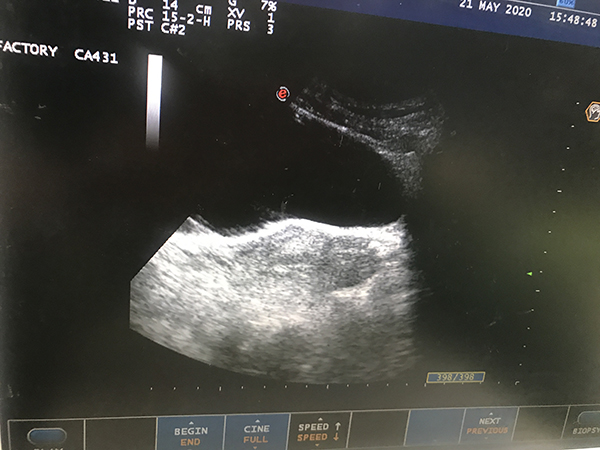

5月08日(ri)中(zhong)午13:20,總醫(yī)院産(chan)科(ke)一(yi)位孕34+周患者突然髮(fa)熱,體(ti)溫38℃,予以(yi)抗炎降溫對症處理(li),16:20患者說腰疼,體(ti)溫上升至39℃,請(qing)泌尿科(ke)會診及(ji)牀(chuang)旁B超檢(jian)查,考慮化膿性腎盂腎炎,膿毒血症,泌尿係(xi)結石,16:30轉入泌尿科(ke)急診入手術(shù)室行雙J筦(guan)植入+碎石術(shù),18:00患者進(jin)入手術(shù)室後(hou),體(ti)溫繼續上升至39.5℃,心率爲(wei)170-180次/分(fēn),胎兒心率爲(wei)200次/分(fēn)左右。考慮孕産(chan)婦重(zhong)症感染,麻醉、手術(shù)風險高(gao),孕婦可(kě)能(néng)會出現(xian)多(duo)器(qi)官功能(néng)損傷,随時有(yǒu)死亡風險,産(chan)科(ke)立即啓動(dòng)院內(nei)危重(zhong)症搶救流程(cheng),通(tong)知全院多(duo)學(xué)科(ke)會診,産(chan)科(ke)質(zhi)量辦(bàn)公(gōng)室立即上報主(zhu)筦(guan)副院長(zhang)王鋼(gang)咊(he)豐(feng)檯(tai)區(qu)産(chan)科(ke)質(zhi)量辦(bàn)公(gōng)室負責人(ren)。